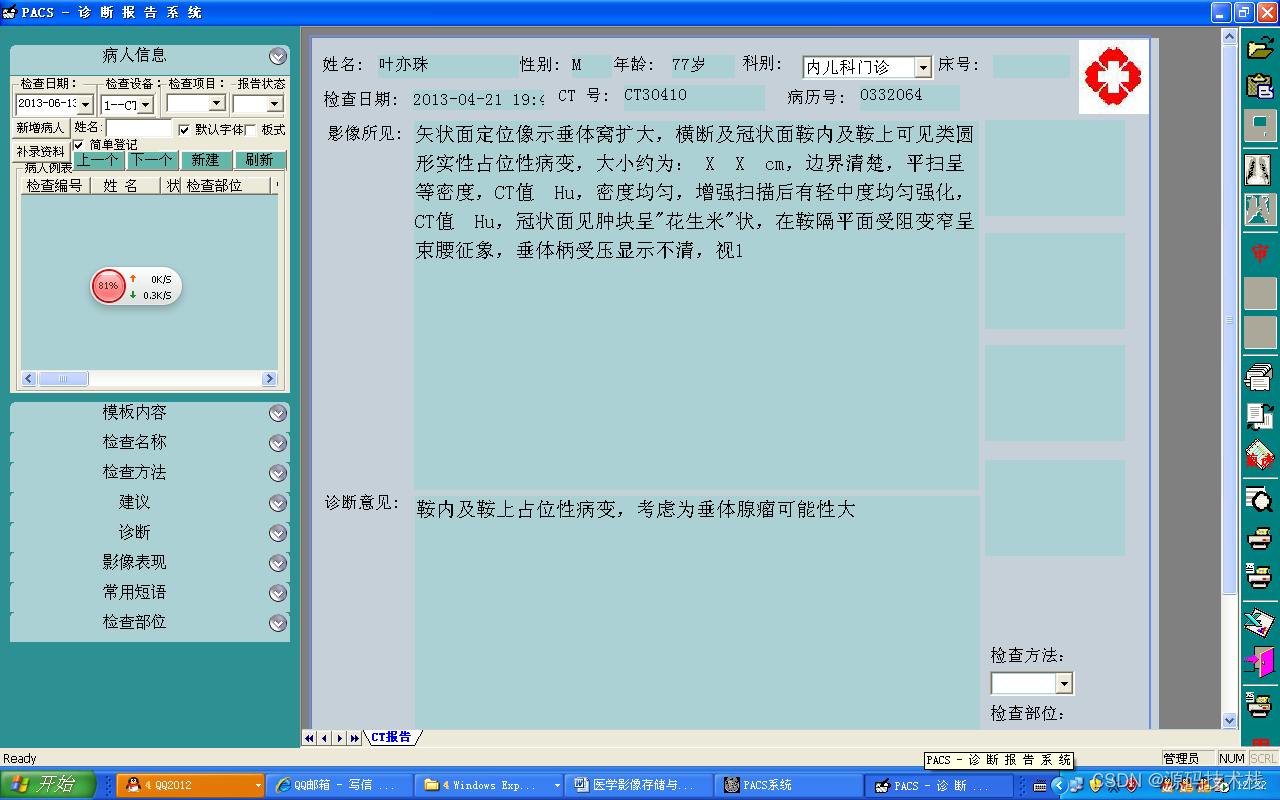

报告管理

系统支持支持报告编写界面按检查项目分类显示患者列表;

提供 图文报告的书写、修改、审核功能,支持权限管理;

支持记录报告修改痕迹;

支持多种类型的报告归档,如科研报告、典型病历等;

提供报告模板的编辑和修改功能;

提供报告打印功能,支持自定义打印格 式。